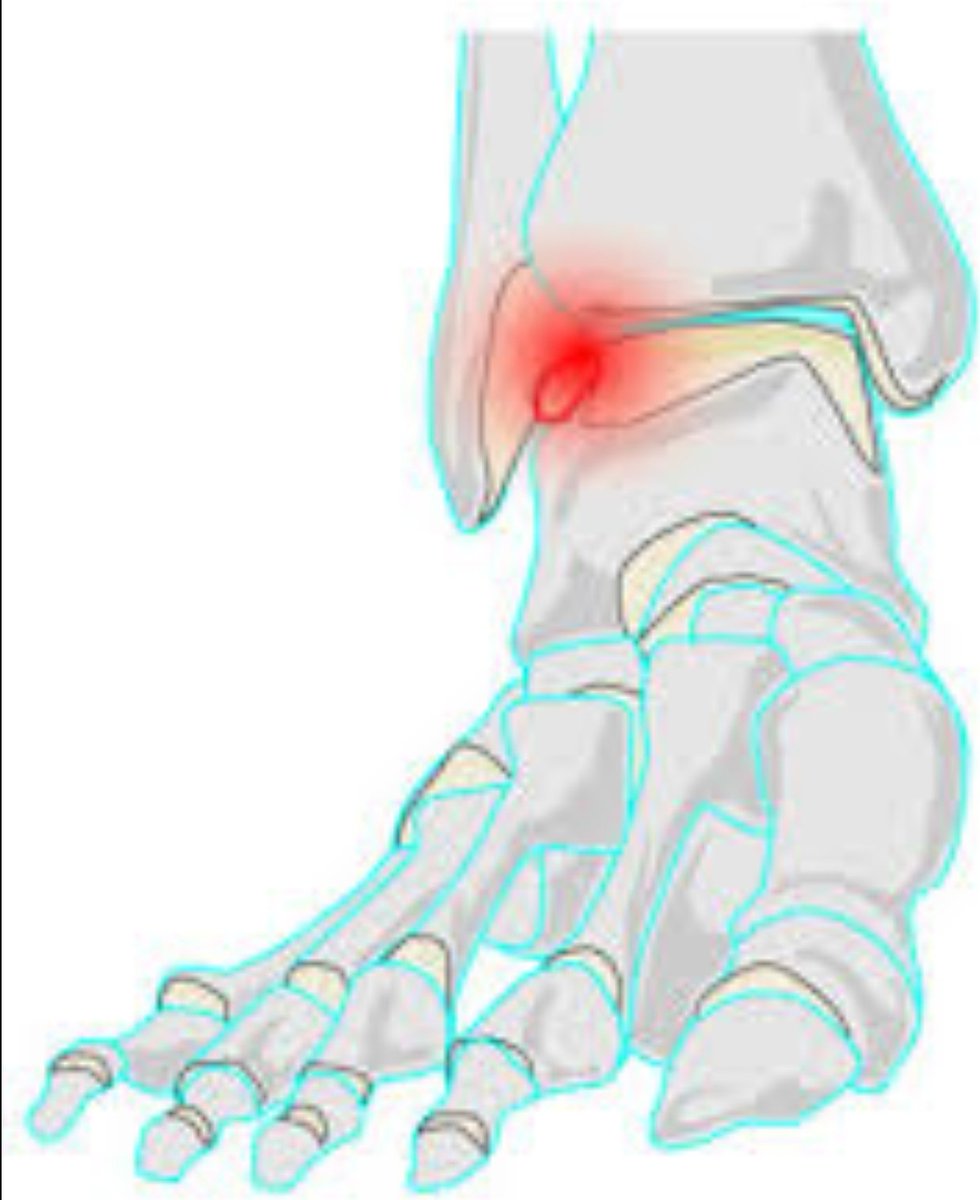

هل عندك ألم بالكاحل أو انتفاخ يروح ويجي؟

قد يكون عندك إصابة في غضروف الكاحل

-انتفاخ في الكاحل، يختفي فتره ثم يعاود الظهور

-ألم بالكاحل عند المشي و ممارسة الرياضة

-في مراحل متقدمة: يكون الألم مستمر

-أصوات وطقطقة بالكاحل